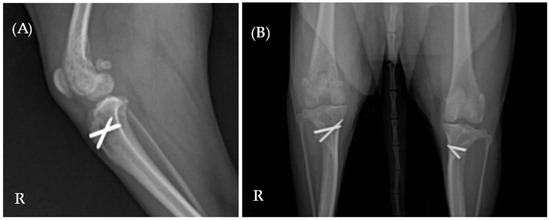

Laboratory results indicated elevated levels of C-reactive protein (CRP) (9.5 mg/dL; reference range 0.1–1.0 mg/dL) and alkaline phosphatase (ALP) (319 U/L; reference range 23–212 U/L). Complete blood count and serum biochemistry, including Albumin (2.4 g/dL [2.3–4.0 g/dL]), Alanine Aminotransferase (ALT) (28 U/L [10–125 U/L]), Blood Urea Nitrogen (BUN) (12 mg/dL [7–27 mg/dL]), Creatinine (1.2 mg/dL [0.5–1.8 mg/dL]), Glucose (94 mg/dL [74–143 mg/dL]), and Total Protein (7.6 g/dL [5.2–8.2 g/dL]) were all confirmed to be within the normal range. Radiographic imaging identified multifocal lesions in the right hindlimb, including osteolysis of the right proximal tibia, a periosteal reaction in the right distal femur, and increased opacity within the right knee joint space (Figure 1). Additionally, reduced muscle thickness was noted at the mid-femur region on the right side compared to the left.

Figure 1. (A) Mediolateral and (B) ventrodorsal radiographic views of the right hindlimb. Multifocal lesions are evident in both the right proximal tibia and distal femur. The letter ‘R’ indicates the right side of the patient.